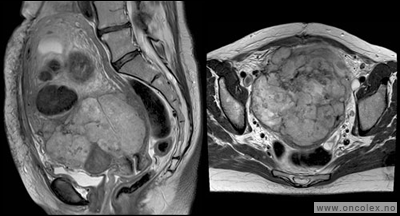

• CT toraks, buk og bekken er standard utredningsmetode ved svulst i buken og på bakre bukvegg, og kan gjøres ved lokalsykehus. De viktigste fordelene ved CT er at undersøkelsen tar kort tid. Innføringen av spiral-CT, og spesielt multislice-teknikk, har forbedret kvaliteten. Røntgen av lungene er som regel tilstrekkelig for å oppdage eller utelukke spredning til lunge.

• MR. Selv om CT foretrekkes når det gjelder buk og bekken, er MR ypperlig tilleggsundersøkelse for å vurdere svulster i bekkenet. Mens pasientens bevegelser reduserer bildekvaliteten av buken og til en viss grad bakre bukvegg, kan MR av bekken være til stor hjelp for å definere omfanget av sykdommen og for å fastsette riktig diagnose i bekkenet.

Typiske funn

Bildeeksempler